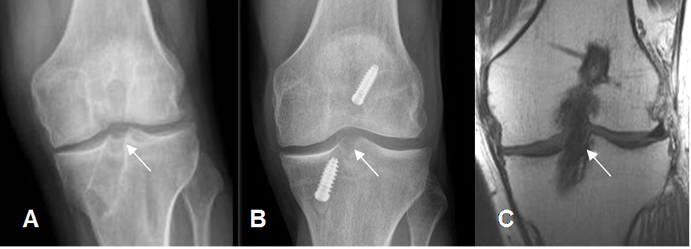

Fig 133. Túnel tibial normal.

A y B: Rx AP y C: RM coronal en T1. Orientación normal del túnel tibial, con abertura

dirigida hacia la región intercondilea.